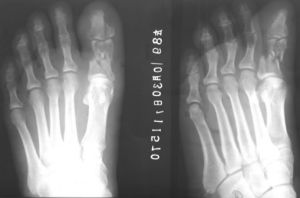

粉碎性骨折屬於完全性骨折,指骨質碎裂成三塊以上,又稱為T或Y型骨折。粉碎性骨

骨折分類及治療方法將骨折範圍在3cm內稱為一般粉碎性骨折,超過3cm者稱為嚴重粉碎性骨折。

骨關節外傷——指粉碎性骨折2、骨裂(醫學上稱為:裂紋骨折):裂紋骨折是眾多骨折中症狀比較輕微的一種,因而常常被忽視。但是,小問題如果不及時治療,也是有可能演變成大問題的。裂紋骨折如果沒有採取恰當的治療,也會發生移位,造成比較大的麻煩。裂紋骨折又稱骨裂,由於沒有明顯的移位,因而無法引起足夠的重視。它一般是由於直接的打擊、撞擊等造成的。